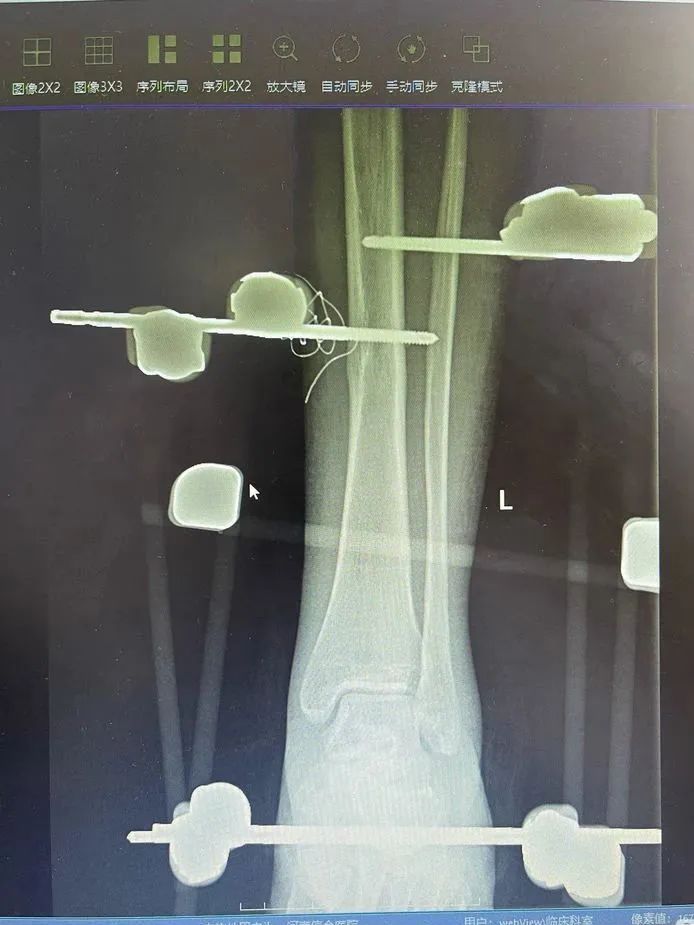

伤者刘女士,32 岁,因突发车祸,导致左踝部不完全离断。入院后,急诊诊断和影像显示,刘女士左踝部不完全离断,距骨游离,外侧软组织缺损、挫伤,胫腓韧带、跟腓韧带、距腓韧带、外侧副韧带等断裂,胫前动脉撕裂,肢体远端循环差。

「三十二岁,正是人生的黄金时期,不能让她把后半生全放在轮椅上,」在急诊科、麻醉科、手术室等多学科密切配合下,以最短的时间,为伤者进行了一期保肢手术(扩创术+韧带修复术+胫前血管吻合术+外固定架固定术+VSD 覆盖创面术)。

随着韧带、血管、神经被一根根微不可见的缝合线慢慢缝合、修复,严重内扣的脚掌被复位、固定,原本苍白的左脚逐渐恢复血色,手术室的所有人都松了一口气,刘女士的左脚,保住了!